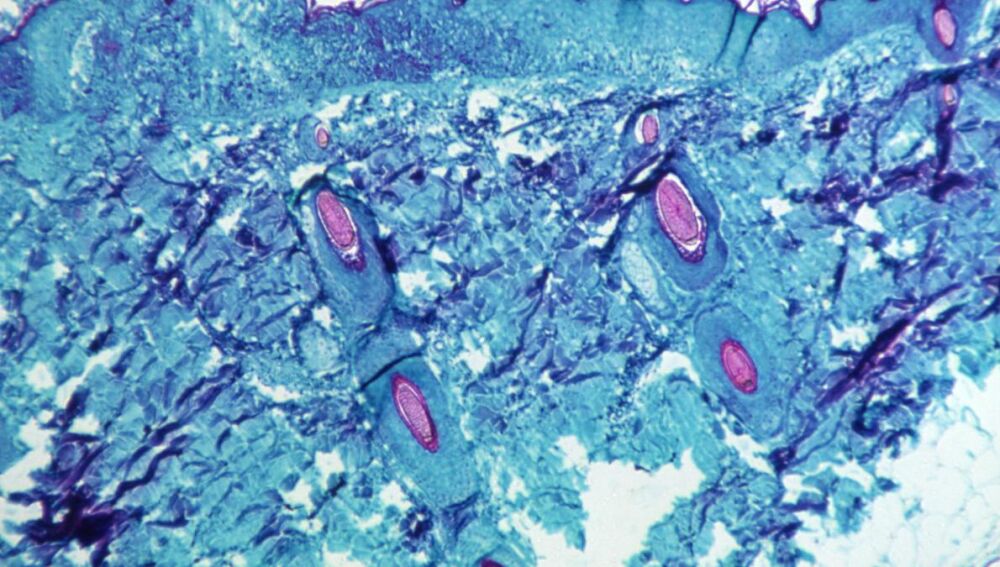

Viruela del mono | Reuters

La viruela del mono es una zoonosis selvática con infecciones humanas que generalmente ocurren en partes boscosas de África Central y Occidental. Una zoonosis es una enfermedad infecciosa que pasa de un animal a humanos: normalmente, son bacterias, virus o parásitos.

El cuadro clínico inicial de una persona contagiada con viruela del mono suele incluir fiebre, dolor de cabeza, dolores musculares, inflamación de ganglios y cansancio. Entre 1 y 5 días después de la fiebre, se desarrolla una erupción, que evoluciona secuencialmente de máculas a pápulas, vesículas, pústulas y costras que se secan y se caen. Estos son otros síntomas comunes asociados a la enfermedad:

Muchas de las personas infectadas examinadas en el estudio presentaban síntomas no reconocidos en las definiciones médicas actuales de la viruela del mono. Estos síntomas incluyen lesiones genitales únicas y llagas en la boca o el ano.